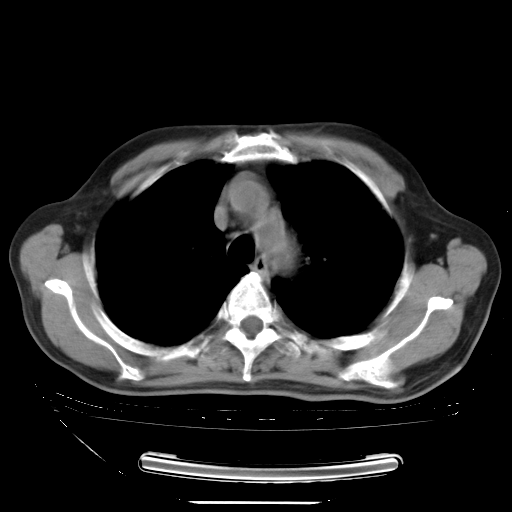

今天复查肺部CT,发现双肺广泛磨玻璃样改变。所以我把3月19日和5月9日相隔50天的肺部CT上传。请大家会诊。

2009年3月19日肺部CT片。

5月9日肺部CT(在4月27日齐鲁医院肺部CT描述部分肺组织磨玻璃样改变,12天后肺组织广泛磨玻璃样改变)

大致读了系列胸部CT:纵隔窗无明显异常,肺窗:从4、27至今:主要是双肺中下野外带可见毛玻璃样改变,目前处于急性肺泡炎阶段,至于原因考虑1、结替组织或胶原血管性疾病所致?2、恶性疾病如恶组在肺部所致的表现或细支气管肺泡癌?3、药物或其它原因如肺蛋白沉着症所致肺泡炎目前不太可能?总之,明天就去请我院的呼吸科、感染科、血液科和临免专家会诊哈。